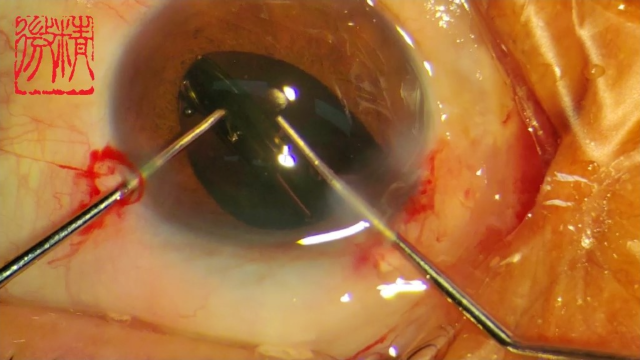

号外号外,湖南省人民医院副院长祖雄兵和眼科主任医师曾琦被指存在不正当关系,并有不雅视频传出。对此,医院工作人员回应:组织正在调查,请给医院宣传部门联系。当地卫生健康委员会对此回应:暂未接到相关的信访反映。祖雄兵为湖南省人民医院副院长,泌尿外科学科带头人。曾琦,博士,主任医师,硕士研究生导师。现任湖南省人民医院眼科副主任、眼科一病区主任,湖南省卫生健康高层次青年骨干人才,湖南省预防医学会眼病防治专业委员会主任委员、湖南省女医师协会眼科专业委员会主任委员、湖南省医学会眼科学专业委员会防盲学组副组长、湖南省医学会眼科学专业委员会眼外伤及职业病学组副组长、湖南省医学会眼科学专业委员会白内障学组副组长、